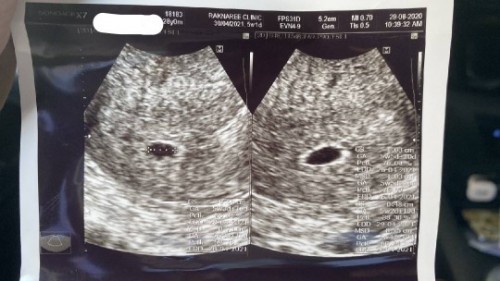

ซาวด์เห็นถุงไม่เห็นเด็ก

แม่ๆท่านไหนเคย ซาวด์ทางช่องคลอดช่วงอายุครรภ์ 5วีคบ้างไหมคะ เราซาวด์เจอแต่ถุงตั้งครรภ์ไม่เจอตัวเด็กคุณหมอบกว่า อาจะเพราะอายุครรภ์ น้อย หรือ ท้องลม... เราใจไม่ดีเลย 😭😭#ท้องแรกคะ